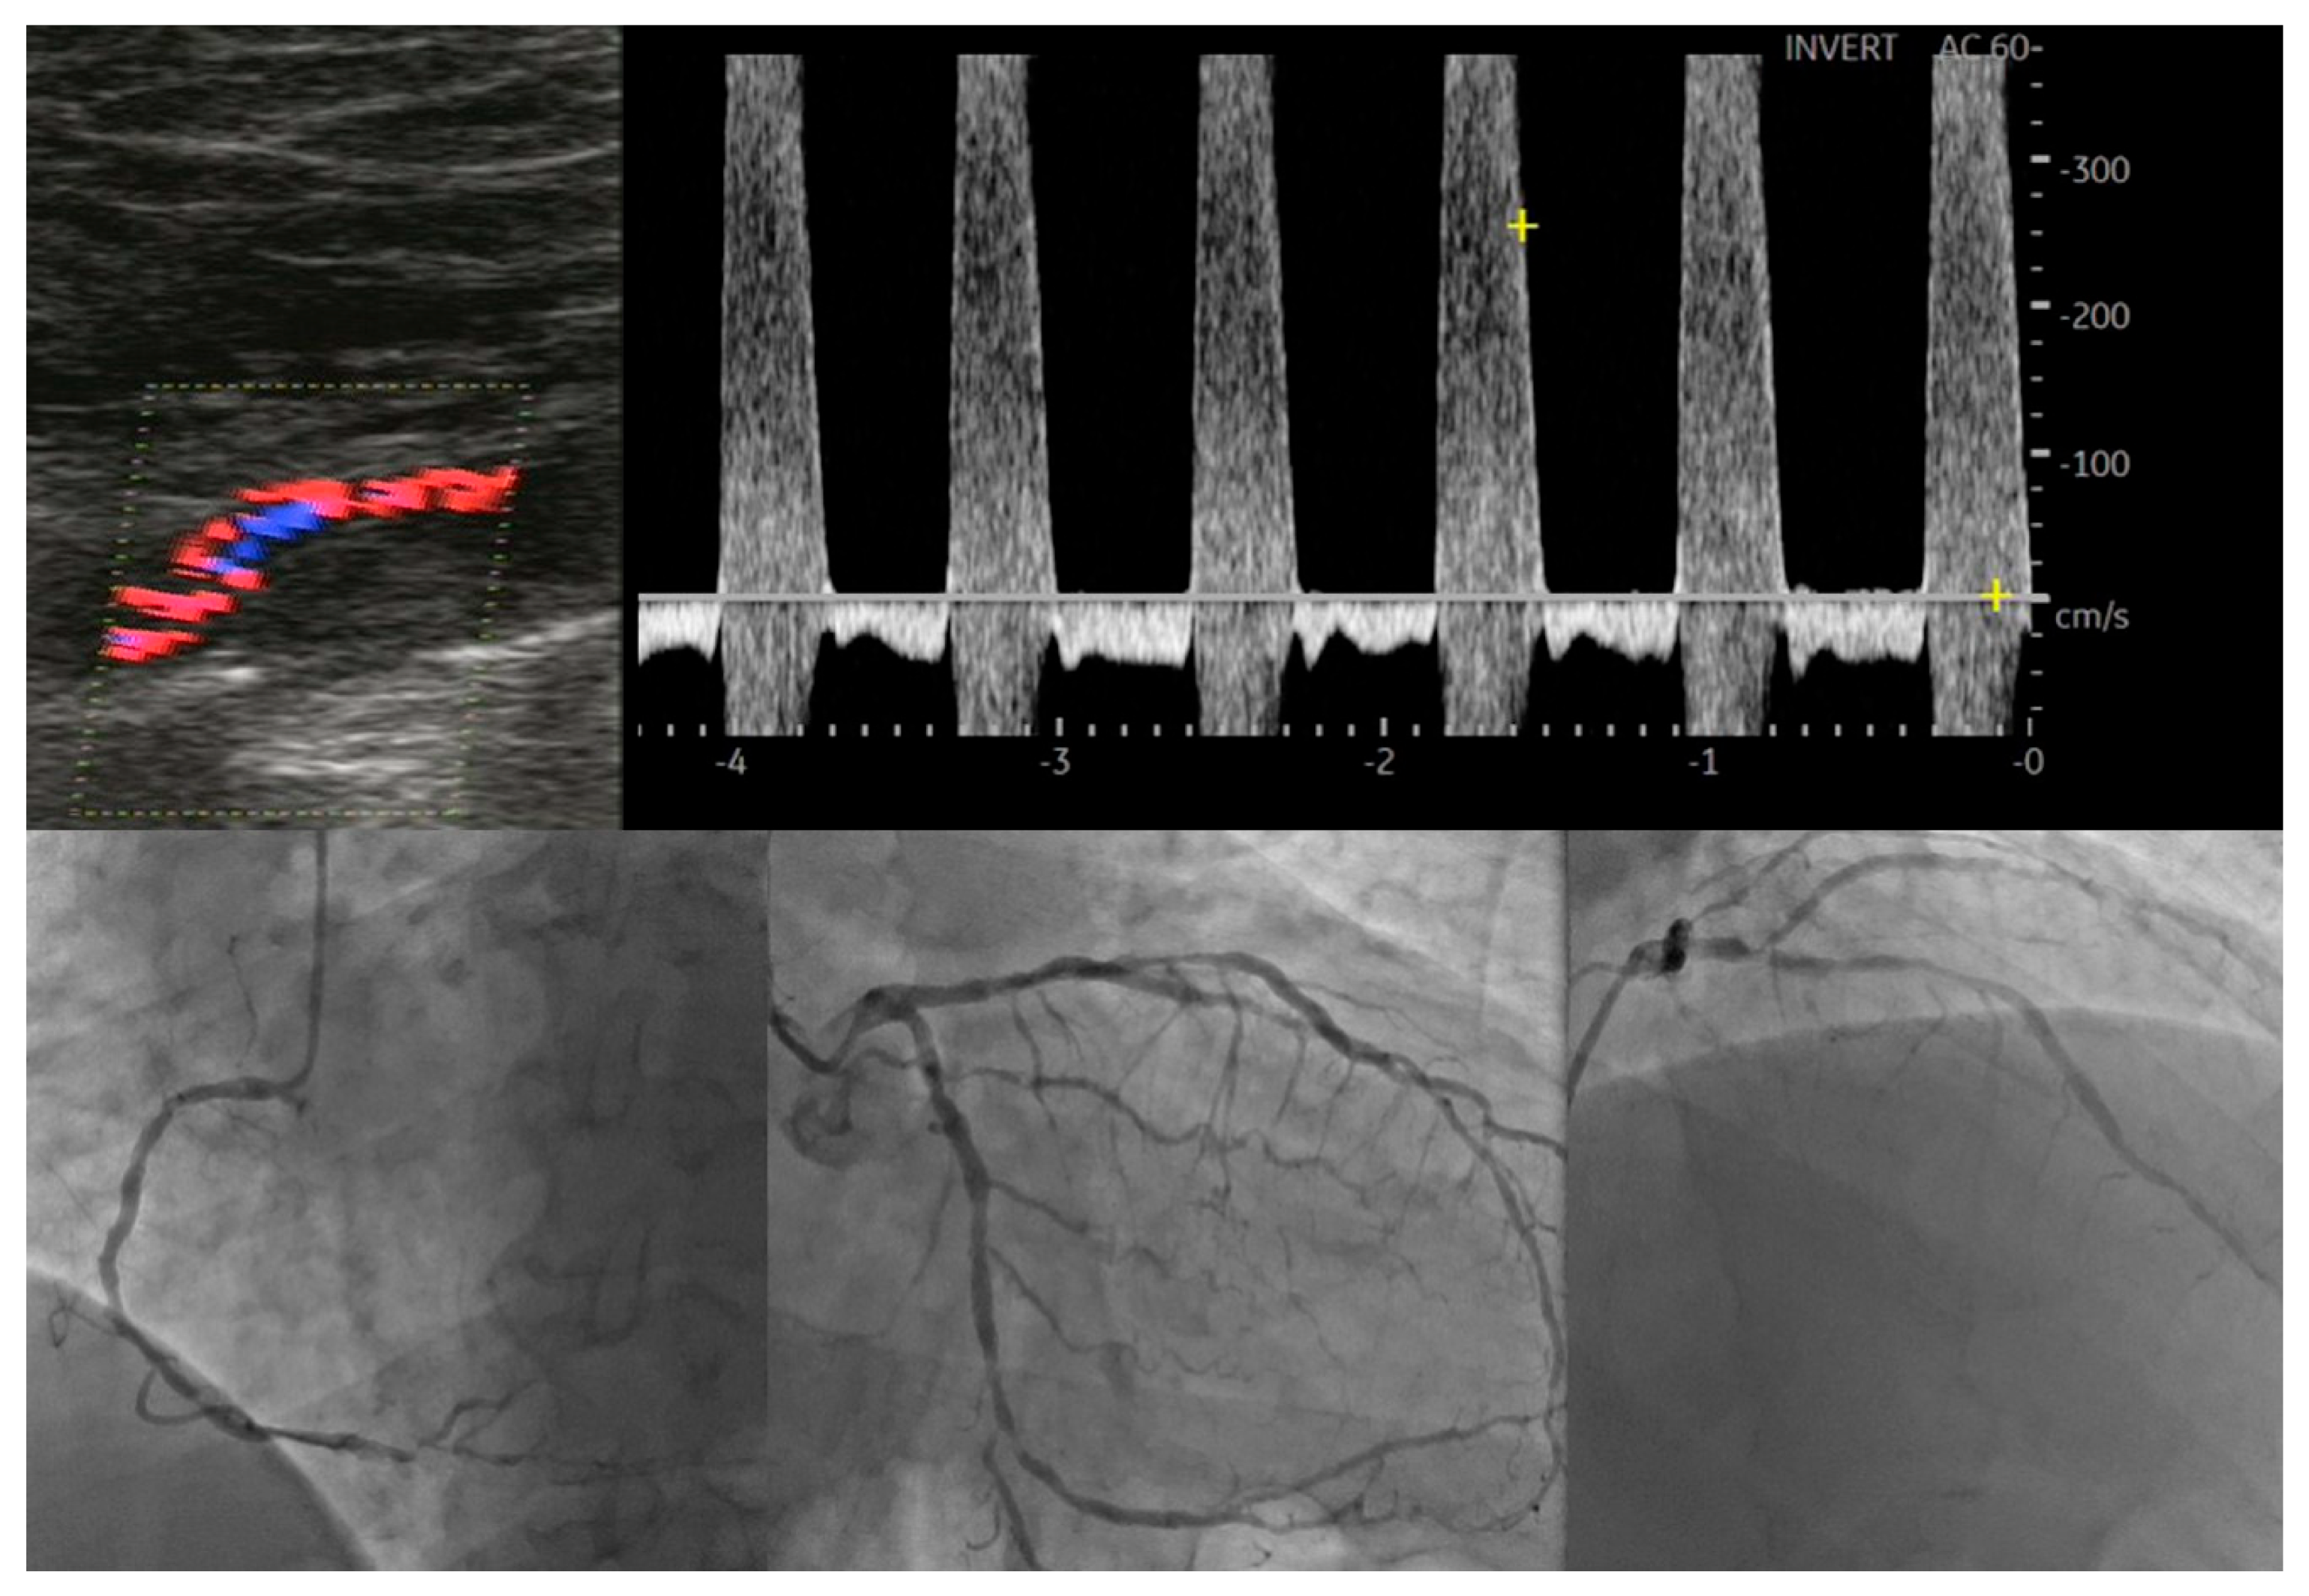

- Tătaru, D.A.; Olinic, M.; Homorodean, C.; Ober, M.C.; Spînu, M.; Lazăr, F.L.; Onea, L.; Olinic, D.M. Correlation between Ultrasound Peak Systolic Velocity and Angiography for Grading Internal Carotid Artery Stenosis. J. Clin. Med. 2024, 13, 517. [Google Scholar] [CrossRef] [PubMed]